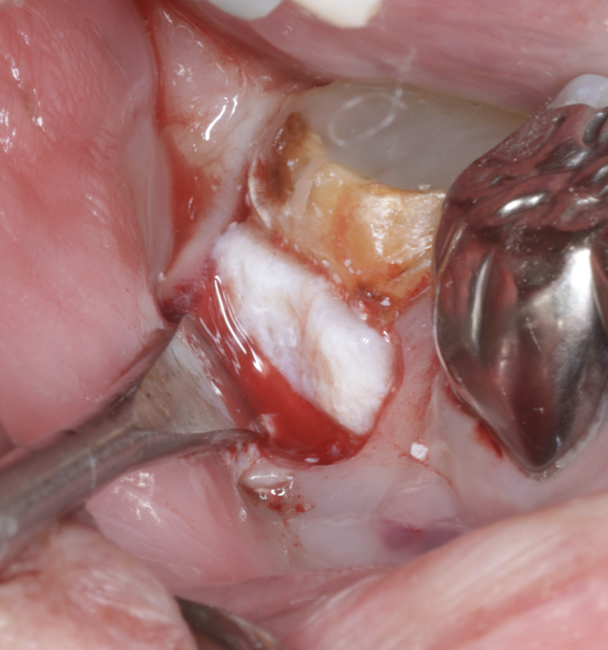

X線・CTにより、歯根分岐部に進行した骨吸収を確認。

骨支持の喪失が見られましたが、根面・感染範囲を精査し、再生療法の適応と判断しました。

治療中

| 治療内容 | 精密根管治療後、以下の流れで再生療法 ・感染組織と不良肉芽を除去 ・根面滑沢化(バイオフィルム除去) ・エムドゲイン®+骨補填材による再生誘導 ・縫合・閉鎖で再生環境を安定化 |